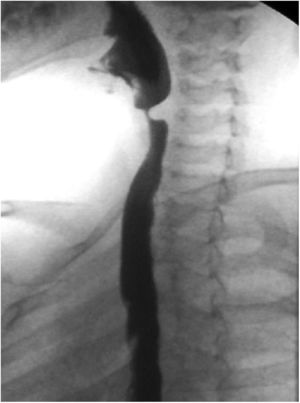

Ante el diagnóstico de acalasia cricofaríngea, el manejo terapéutico consistió en 4 inyecciones intramusculares de toxina botulínica (10 unidades por inyección) a nivel muscular. Tras ello, el paciente mostró mejoría clínica (con desaparición de las crisis de atragantamiento y rumiación), así como radiológica (fig. 2).